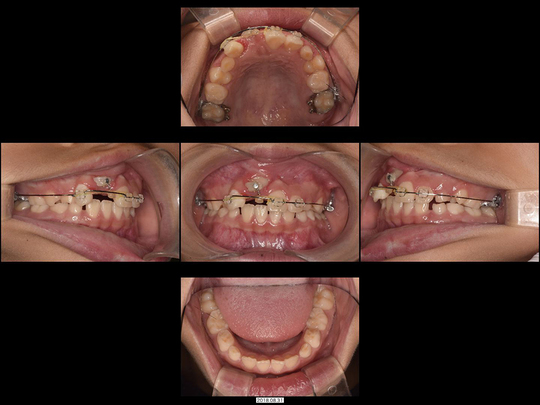

Wさん 開始時8歳 女性

矯正治療中

前歯がねじれているのを改善したいというご希望でした。「抜歯するしかない」と診断されるような状態です。

固定式の拡大装置を用いて前歯と奥歯の永久歯が生え変わるスペースを作り、正しい歯並びと咬み合わせに誘導(咬合誘導)しました。非抜歯・ワイヤー矯正なしで終了できています。

36か月、36回

462,000円

リスクや副作用:装置に慣れるまでに1週間ほどかかる可能性があります。歯列を広げる過程で少し痛みを感じる可能性があります。装着時に多少しゃべりづらくなる可能性があります(2~3週間ほどで慣れます)。